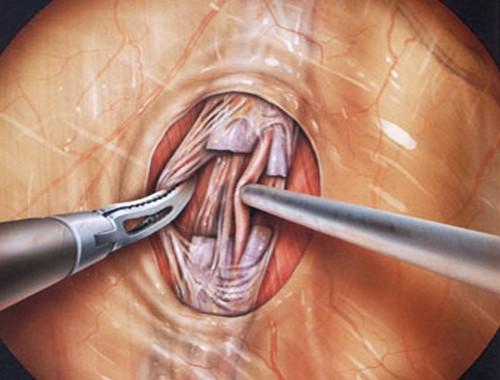

درمان واریکوسل با جراحی لاپاروسکوپ

عملیات بالا همچنین می تواند به صورت یک روش لاپاروسکوپی (از طریق برش های کوچک با یک دوربین) و از طریق سه برش کوچک در شکم برای عبور لولهها انجام شود. جراحی لاپاروسکوپی از طریق لولههای نازک که از طریق یک برش کوچک به بدن وارد میشود، انجام میگردد. ابتدا درون بدن با گاز برای دید بهتر پر شده و سپس جراح از یک دوربین مخصوص قرار گرفته انتهای لوله دستگاه برای دیدن داخل بدن استفاده میکند. جراحی لاپاروسکوپی نیز تحت بیهوشی عمومی انجام میشود.